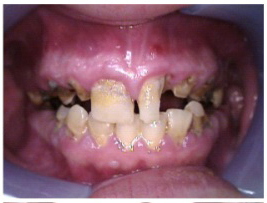

Often, the most visually striking manifestation of long-term meth use—known as “meth mouth”—is caused by the lack of saliva combined with an increase in soda drinking and extremely poor oral hygiene. This typically leads to meth abusers experiencing a large amount of caries. Decay begins with occlusal and facial caries and progresses rapidly, decaying to the bone level and often leaving only roots (Figure 1 through Figure 3).16

Fig 2. Gross oral destruction was the result of more than 20 years of meth use in this 41-year-old woman.

Figure 2